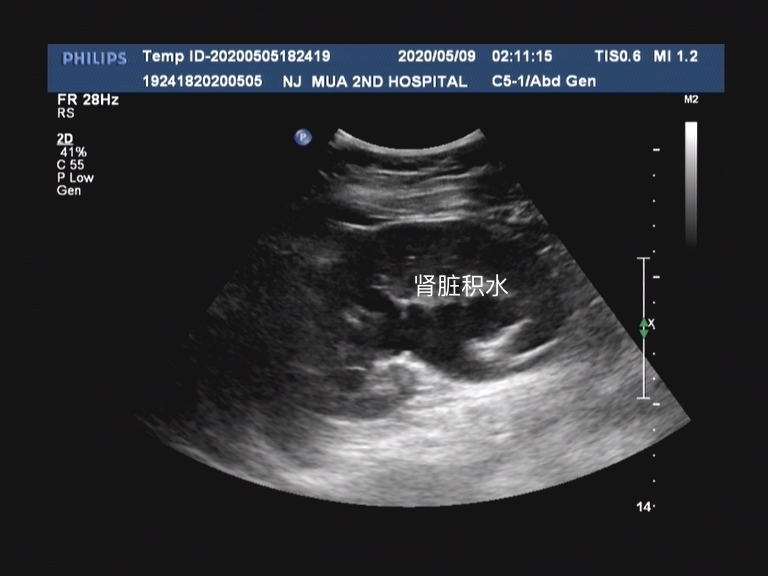

输尿管结石急性发作的疼痛是很多人不能耐受的,往往为了明确诊断,首选的检查方式也是彩超检查,因为做CT的费用较高,同时需要憋尿后才能检查,所以很多病人会选择彩超。但是这也带来一个问题,就是中下段的输尿管结石,因为人体的肥胖和脏器的阻隔,往往不能明确看到输尿管结石,这个时候往往我们会看另外一个指标,就是输尿管积水。因为输尿管是作为连接肾脏和膀胱,传输尿液的通道,如果有结石梗阻以后,在结石上方的输尿管就会因为尿液不能顺利排入膀胱而出现肾脏积水情况。如图中所见,肾脏形态中间的黑色区域就是肾脏积水。一般肾脏积水还会表现在排尿障碍、输尿管病变的患者中。

肾脏积水在彩超上是低信号,就是黑色的部分